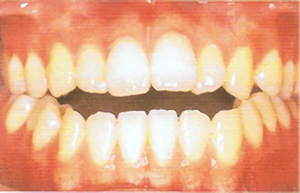

type02

• 口を閉じると、下の歯列が上の歯列よりも前に出ている

• 顎がしゃくれている

• 下顎が発達しすぎている

• うまく咀嚼できない

• 言葉が聞き取りにくい、と言われることがある

「反対咬合(はんたいこうごう)」である可能性があります。一般的には「受け口」と言われます。遺伝的な要因もありますが、上唇を噛んだり、舌を突き出す等の癖が原因になっていることがあります。